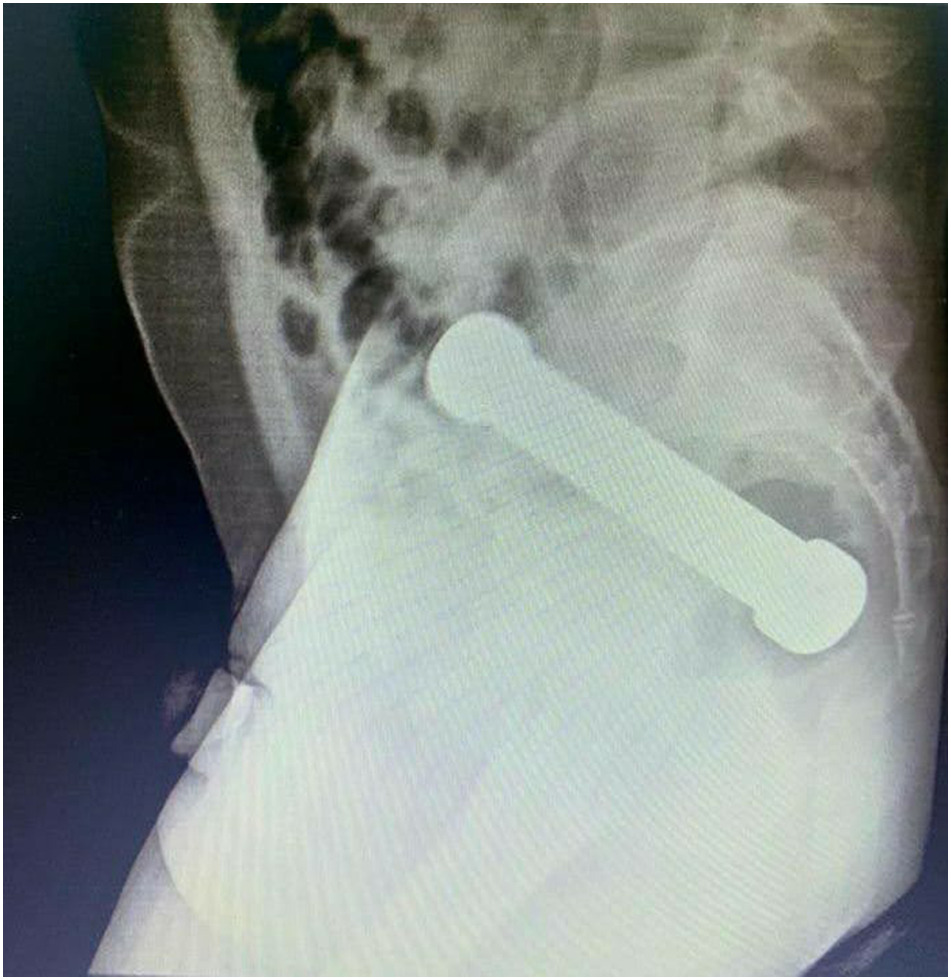

Sin embargo, las radiografías abdominales revelaron que el hombre tenía una mancuerna de 20 centímetros atorada a la altura donde el colon se conecta con el recto.

Posteriormente, el sujeto confesó que dos días antes se había introducido el objeto metálico de dos kilos sin lograr sacarlo después de su interior.